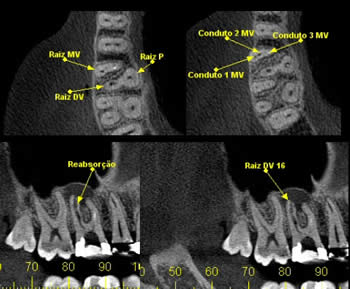

• Endodontia

Para verificar obturação dos canais radiculares, visualizar canais acessórios, perfurações, reabsorções e avaliação de fraturas radiculares.

Caso 6: Reabsorção

Achado radiográfico, na radiografia periapical de rotina, nota-se área de menor densidade na distal cervical e alteração no contorno na mesial, e rarefação óssea periapical. Ao exame tomográfico pode-se observar o dente 11 com osteólise apical e área de reabsorção na distal e reabsorção por substituição na mesial.